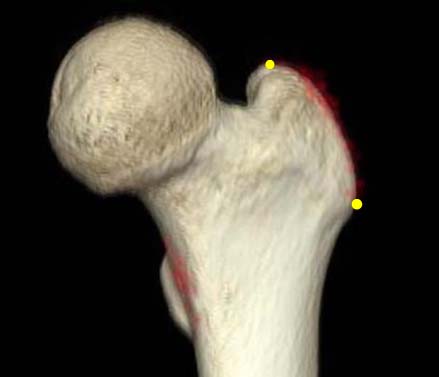

*Vertical distance from greater trochanter to fracture line. †Vertical distance from proximal boundary of lesser trochanter to fracture line. ‡The angle between the fracture line of the distal fragment and anatomical axis of the femur.